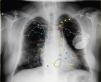

A 64-year-old male with idiopathic cardiomyopathy and atrial fibrillation, previously fitted with a cardioverter-defibrillator (ICD) using a persistent left superior vena cava (PLSVC) for lead placement, was scheduled for upgrade to a cardiac resynchronization therapy-defibrillator due to new-onset left bundle branch block, heart failure and severely depressed left ventricular (LV) ejection fraction. A selective venogram of the coronary sinus from a left-sided approach revealed a sharp angulation of a lateral subsidiary target vein, precluding placement of the LV electrode in an optimal position, and leading to non-controllable diaphragmatic stimulation. A solution was devised by accessing the right subclavian vein and culminating in subcutaneous tunneling of the lead to the contralateral generator pocket. A control chest X-ray with explaining diagram (Figure 1) shows the right ventricular defibrillator lead (yellow arrowheads and dashed yellow line) following a standard left subclavian vein (LSCV) approach but going through a PLSVC draining to the coronary sinus (CS), then entering the right atrium (RA) and crossing the tricuspid valve, with its tip abutting the right ventricular (RV) apex. The LV lead is seen sequentially entering (blue arrows) the right subclavian vein (RSCV), superior vena cava (SVC), RA, CS and lateral vein. Finally, the end of the proximal LV lead (asterisks) is tunneled subcutaneously and connected to the previously placed generator in a left prepectoral position.